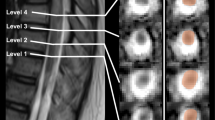

Fifty adult Sprague-Dawley rats were grouped as: (A) sham-operated group (n = 10); (B) SCI without HBO therapy group (n = 10); (C) SCI with HBO therapy for 2 weeks (SCI+HBO2W) group (n = 10); (D) SCI with HBO therapy for 4 weeks (SCI+HBO4W) group (n = 10); (E) SCI with HBO therapy for 6 weeks (SCI+HBO6W) group (n = 10). Basso Beattie Bresnahan (BBB) scores and diffusion tensor imaging parameters including fractional anisotropy (FA), mean diffusivity (MD), radial diffusion (RD), and axial diffusion (AD) values in the injury epicenter, as well as 2 mm rostral and caudal to the injury epicenter were collected and analyzed 6 weeks post-injury.

Higher BBB score and FA values were found in the SCI+HBO4W group than in the SCI and SCI+HBO2W groups (all P < 0.05), whereas no significant differences of these metrics were observed between the SCI+HBO4W and SCI+HBO6W groups. MD and RD values of the SCI+HBO4W group were significantly lower than those of the SCI group (all P < 0.01). FA values were positively correlated with BBB scores. MD and RD values were negatively correlated with BBB scores.

DTI parameters, especially FA, could non-invasively and quantifiably evaluate the efficacy of HBO treatment for rats with SCI and 4 weeks may be the more appropriate treatment course.